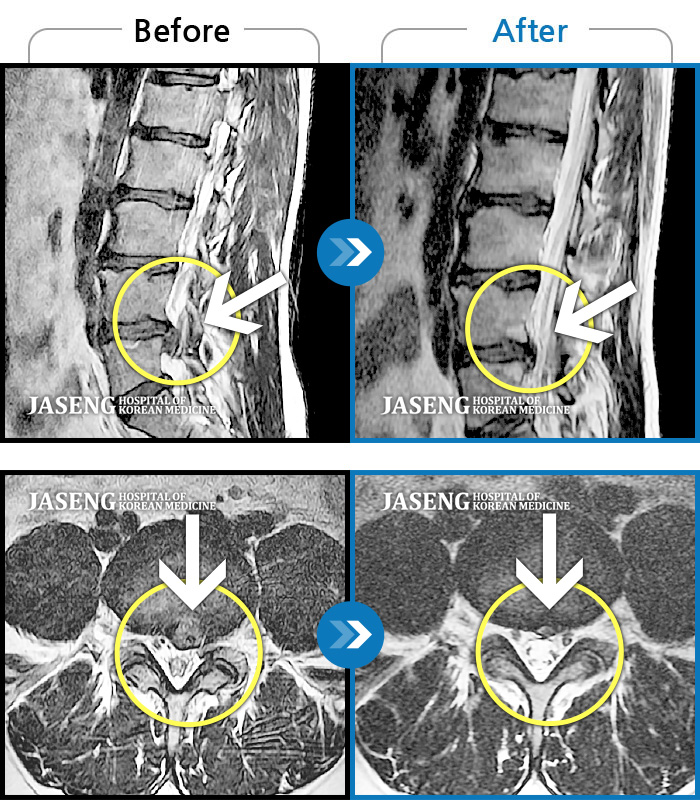

처음엔 이곳저곳 아파서 확실하게 어디가 아팠는지 몰랐는데 사고 후 일주일쯤 될 무렵 MRI촬영후 정확하게 진단을 받았습니다

허리디스크 2단계(초기) 진단을 받긴 했으나 다행히 근육량이 많아 모르고 살았는데 사고로 인해 디스크에 상처가 생겨 힘든 나날을 보내고 있습니다

70대 어머니가 디스크파열로 수술을 당장해야한다는 큰병원의 권유를 뒤로하고 자생을 결정하고 엄봉군원장님을 만났습니다. 두달여 치료받고 많이 호전되었고 갈때마다 진심을 다하시는 원장님으로 인해 정서적인 치료도 받고 있답니다 앞으로도 잘 부탁드립니가!!

디스크수술만 두번했어요 사고때문에 생긴 통증때문에 걱정이 많았어요 엄원장님 설명도 알기쉽게 해주시고 환자에대한 배려가 참 많은 분이셔서 많은 도움을 받고있습니다 적절한 치료처방으로 상태도 많이 호전되어 더 신뢰가가고 너무 감사해요 이렇게남아 감사의 글을 드립니다